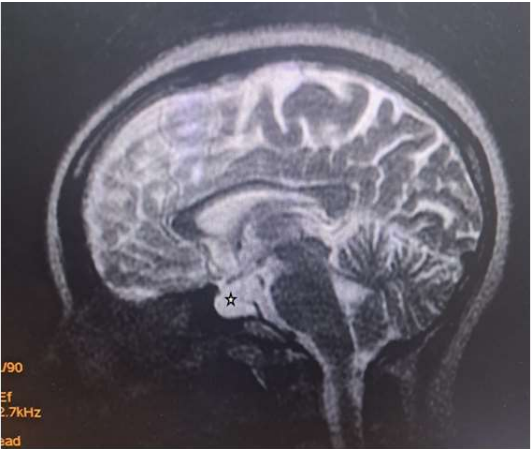

Magnetic Resonance Imaging (MRI) revealed expansion of the sella with a well-defined fairly rounded lesion measuring 15 X 14 X 15mm (width X AP X H). It is hypointense on T1W, hyperintense on T2W and suppressed on FLAIR sequence. Rim enhancement is seen post contrast. The mass is inseparable from the optic chiasma suggestive of compression.

Figure 4: Sagittal T1W image of the brain showing a hypointense rounded intrasellar mass lesion (white asterisk) with obliteration of the optic chiasma (white arrow).

Figure 5: Sagittal T2W image of the brain showing a hyperintense rounded intrasellar mass lesion (black asterisk).

Due to its high soft tissue resolution, Magnetic Resonance Imaging (MRI) is the primary diagnostic technique for RCC9. It also determines the cystic content and fluidity of the cyst which is useful in planning for subsequent patient’s management10. Fifty percent are hyperintense on T1W (due to high protein content) while 50% are hypointense. On T2W, 70% are hyperintense, 30% iso or hypointense and 20% have hypointense rim. T1W Post contrast images usually show no enhancement. However, a thin enhancing rim may be seen when cyst wall infection is present [19-20]. The case presented revealed expansion of the sella with a well-defined fairly rounded lesion measuring 15 X 14 X 15mm (width X AP X H). It is hypointense on T1W, hyperintense on T2W and suppressed on FLAIR sequence. Rim enhancement is seen post contrast. The mass is inseparable from the optic chiasma suggestive of compression. The appearance of the cyst confirmed no haemorrhage or debris within the cyst. However, the rim enhancement suggest inflammation of the cyst as explained in the text. The finding of optic chiasma compression may explain the visual impairment and the bitemporal hemianopia seen in the patient.